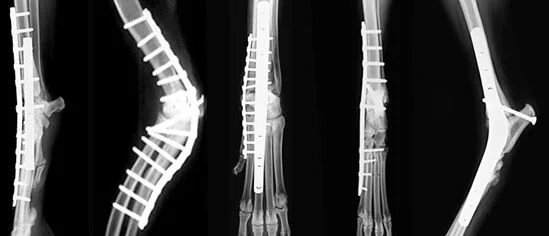

Операция суставов собак